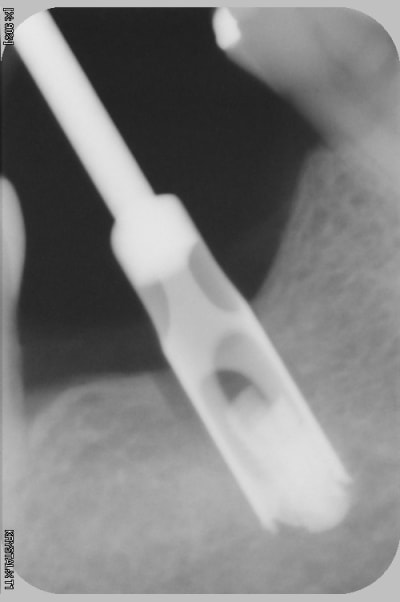

l'erreur vient dans ce cas pas du guide mais de mon inexpérience, le maillon faible ( de RENOUARD) c'est moi.

et là mauvaise nouvelle, j'ai voulu sortir l'implant , mais l'implant s'en va pour trois mois. va falloir sortrir la fraise à os, l'insert diamanté, et les loupes

à mon avis tu augmenter fortement tes problèmes si tu attends 3 mois, l'os peut se reformer et tu ne trouveras plus ton implant.... si tu stress trop avec le patient, fais toi assister par un confrère le patient ne t'en voudra pas.

2 solutions: soit retirer l'implant soit faire une empreinte et faire faire un pilier long (titane) lisse qui va transformer ton implant en transosseux/transmuqueux... si tu n'as pas de ciment pour la jonction c'est tout à fait jouable.

soit tu t'amuse à l'enlever (le plus simple est de trouver un outil long et de dévisser, ou bien: le trépan....

perso j'irai le chercher de suite...

pour moi la solution peut etre l'utilisation d'un tourne à gauche à la clé à main.

si l'espace interdentaire le permet.

comme les autres, je te conseil d'agir au plus vite.

si nécessaire meuler l'épaulement pour insérer à nouveau le porte implant ainsi tu as les 2 possibilités ou remonter en rotation ou en traction puisque la vis le maintiendra à l'implant.

oui finalement, lambeau , j ai enlevé de l os à la fraise, puis à la fin avec un insert à boule diamantée, pour finir sans abîmer la tête de vis ( conseil que j avais lu sur eugenol). Puis j ai mis une grosse vis de cicat.

Trois semaines plus tard j ai fait mon empreinte puis mis la couronne scellée (,cvimar) sur pilier vissé